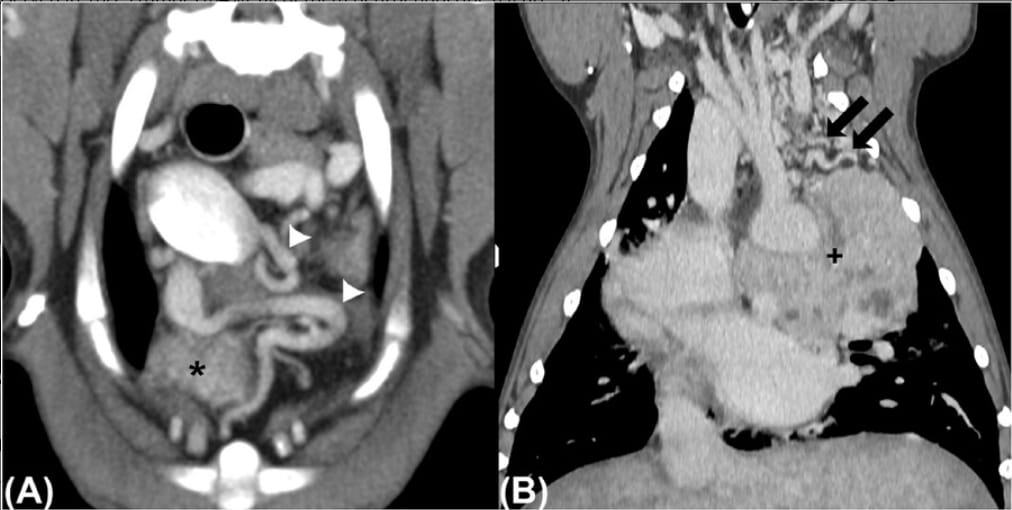

A, Transverse postcontrast CT image of a dog with an ETC showing the presence of tortuous neovascular formation (white arrowheads) in the cranial mediastinum and surrounding the cranial aspect of the HBT (*, only partially included). B, Dorsal plane reconstruction of a dog with a nonspecific neuroendocrine HBT (+) and multiple small tortuous vessels (neovascularization) mostly located cranial to the mass (black arrows